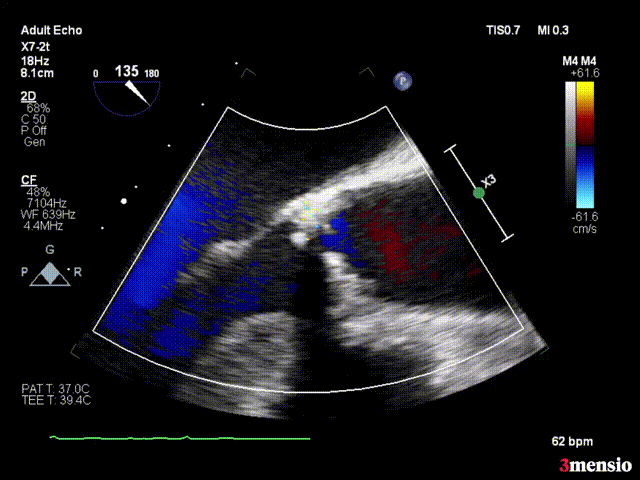

术前心脏超声结果显示,患者主动脉瓣开放明显受限,呈二叶式畸形(Type 0型),主动脉瓣前向血流Vmax 5.82m/s,平均跨瓣压差84mmHg。

超声心动图1